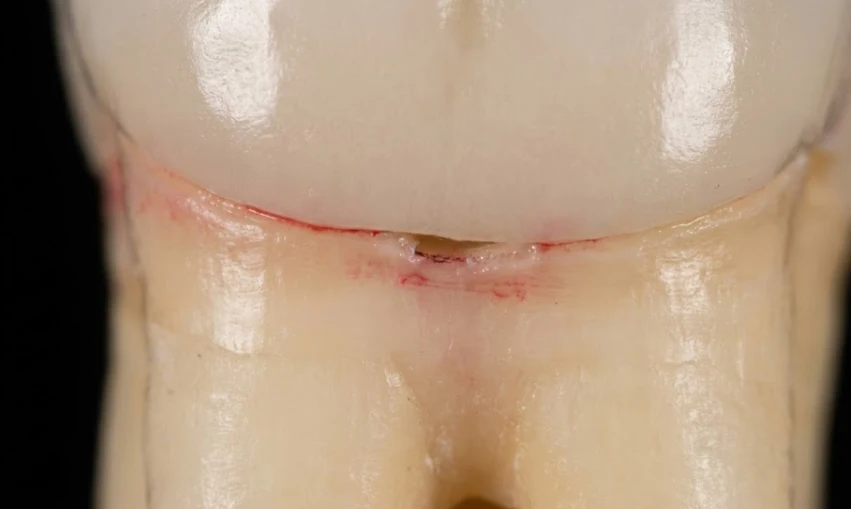

щель, через которую проникает кариес под коронкой

Что вызывает бактериальное вторжение? Обычно это происходит у «края» — той крохотной, почти невидимой линии, где коронка встречается с вашим натуральным зубом.

За многие годы зубной цемент может ослабнуть. Кроме того, при неправильной гигиене полости рта, рецессия десен может привести к обнажению более мягкой поверхности корня под коронкой. В результате формируется микроскопическая щель. Бактерии настолько малы, что могут проникнуть даже через очень мелкий трещину.

3. Следите за деснами: Если десна вокруг определенной коронки постоянно красная или кровоточит при чистке, это не просто гингивит. Возможно, под коронкой нарушается герметичность.